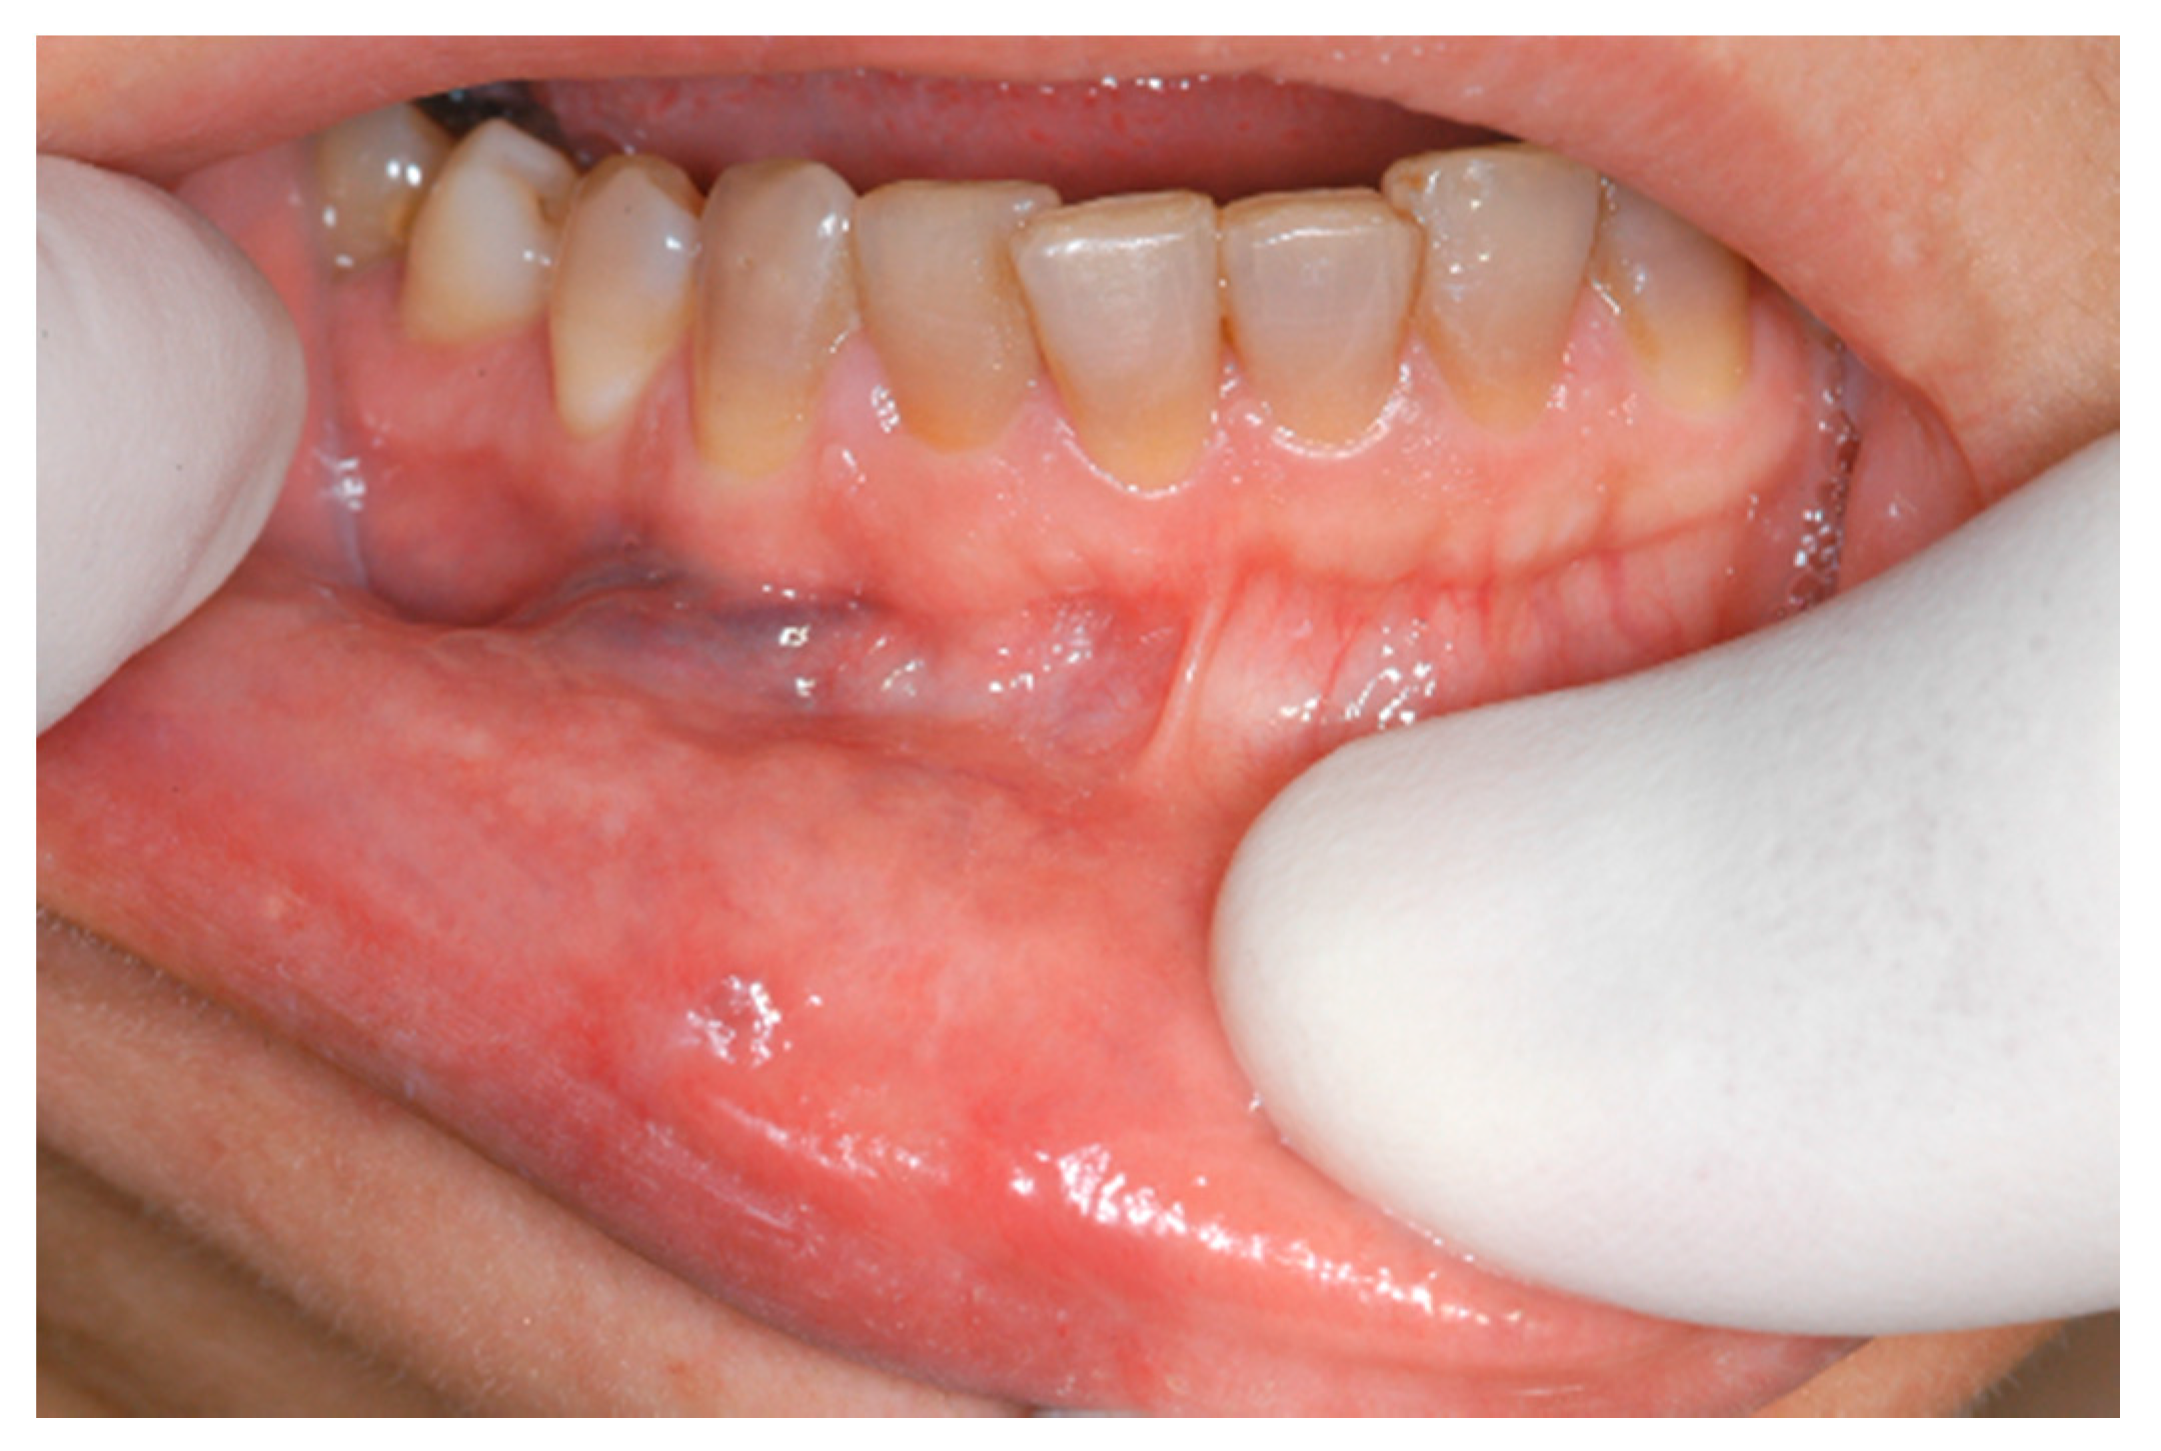

Figure 1.

Clinical aspect of venous malformation (VM) on the lower lip.